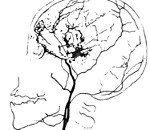

I67.5 Болезнь Мойамойа